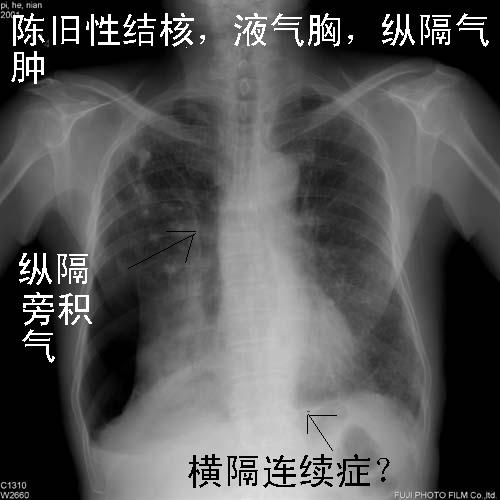

此病人咳嗽\胸闷一周,伴随发热两天.

右肺感染伴陈旧性结核;肺气肿;右侧自发性液气胸。

右侧气胸部分气体位于右上纵隔胸膜腔,右下肺萎陷且密度不均匀还应考虑肺内或者胸膜病变,建议结合侧位片,右上肺结核以纤维增殖灶和钙化灶为主,

另外,纵隔气肿.

右肺感染伴陈旧性结核;肺气肿;右侧自发性液气胸(多房性,胸膜粘连所至)